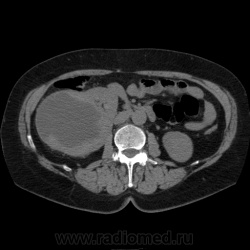

Солитарное кистовидное образование правой почки с неравномерно утолщенными стенками, у узлами в капсуле, накапливающими контраст. Фасция Гарота справа тяжистая. По классификации - киста 4-й категории, крайне велика возможность малигнезации. Может, показалось вовлечение парааортальных лимфоузлов?

В 1986 г. M.A. Bosniak создал “рабочую” классификацию кистовидных образований почек, которая позволяет предположить доброкачественность или злокачественность кистозных образований при распределении их по радиологическим критериям на 4 основные категории. Образования I и II категорий являются заведомо доброкачественными и поэтому нуждаются в динамическом наблюдении или, по показаниям, в лечебной пункции со склеротерапией под контролем УЗИ или КТ. Образования III категории могут быть как доброкачественными, так и злокачественными, а образования IV категории – кистозные почечноклеточные раки.

Третья категория – более сложные кистовидные образования, которые демонстрируют какие-либо радиологические признаки злокачественности. Некоторые из этих образований оказываются доброкачественными (например, сложные кисты, мультилокулярная кистозная нефрома, геморрагические кисты), другие злокачественными (почечные кистозно-клеточные карциномы). Одним из критериев, которые заставляютотнести кистовидное образование почки к III категории, является повышение плотности ее стенки. При КТ у кистовидного образования выявляется плотная (вплоть до обызвествления) стенка по всему периметру кисты, хотя образование может сохранять некоторые признаки простой кисты почки. Следующим критерием является характер отложения кальцинатов. Если при КТ в образовании определяется большое количество кальцинатов, расположенных глыбками (как на периферии образования, так и в центре), если из-за этого стенки и перегородки становятся утолщенными, неправильной формы, то данное образование следует отнести к III категории. Наличие множественных перегородок толщиной более 1 мм, видимых утолщений в месте прикрепления перегородок к стенкам кисты позволяет также отнести данное образование к третьей категории. Большое количество тонких перегородок в образовании определяет его как сложную кисту. Такие образования крайне сложно дифференцировать как доброкачественные или злокачественные, но они чаще по КТ-картине выглядят как злокачественные. При КТ определяется негомогенное многокамерное образование округлой или неправильной округлой формы, возможно с капсулой. Плотность образования неоднородная, пониженная относительно паренхимы, в полости образования видно большое количество перегородок.

IV категория – поражения явно злокачественные, обычно кистозные почечно-клеточные карциномы. Основными симптомами кистозной опухоли при КТ являются: неправильная форма кисты, негомогенность структуры образования с участками некроза, деформация почки, нечеткая граница между кистой и паренхимой почки, плотностные показатели могут быть выше, чем в кистах (+20…+40 Н), т.е. близкие к плотности почечной паренхимы. Капсула имеет неравномерную толщину, часто обызвествлена по периферии. Возможна визуализация дополнительных фокусов образования (кажущееся увеличение образования в размерах и изменение его конфигурации) после введения контрастного вещества. Но самым важным симптомом является увеличение плотности внутреннего содержимого после внутривенного введения контрастного вещества. Часто на серии срезов удается выявить эндофитные гребневидные фестончатые разрастания, выступающие в просвет кистозной полости. Особенно хорошо этот мягкотканый васкуляризированный компонент опухоли проявляется при внутривенном контрастировании

Всё верно, я тоже пользуюсь данной классификацией по Босняку, кистозно-солидное образование правой почки я отнёс к 4 категории, нужно отметить, что преобладает кистозный компонент, но солидный компонент довольно приличный и значительно накапливает контрастное вещество до 80-90HU, четко капсулу образования не отграничить. Ко всему этому в паренхиматозную фазу четко дифференцируются единичные парааортальные и паракавалльные л/узлы. С большей степенью вероятности в данном случае cr почки. Пациентка на следующей неделе будет госпитализирована для верификации.

Описание изменений, выявленных при микроскопическом исследовании: опухоль представлена крупными альвеолярными структурами из светлых, оптически пустых клеток с мелкими гиперхромными ядрами, опухоль частично инфильтрирует капсулу почки, полностью прорастает стенку почечной лоханки, образуя полиповидные структуры. Одиночные опухолевые эмболы в сосудах почки. Отдельно присланный узел представлен тканью почки с опухолевым узлом, строение которого соответствует выше описанной опухоли. В воротах почки патологических образований не найдено. Во всех исследованных лимфоузлах (6 шт.) метастазы опухоли с замещением всей ткани лимфоузлов.

Патоморфологическое заключение: массивный светлоклеточный почечно-клеточный рак почки с частичной инфильтрацией капсулы, прорастанием в ЧЛС, опухолевыми эмболами в сосудах, множественными метастазами в забрюшинные лимфоузлы (6 шт